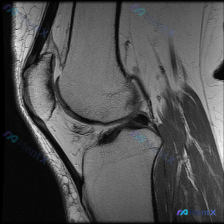

看到这个膝关节读片的病例,整理了完整信息和分析思路分享给大家。 病例基本信息 核心问题:临床怀疑膝关节存在软骨异常,提供单张膝关节矢状位MRI,请分析图像中的明显发现。 影像基础信息 这是一张清晰度良好的膝关节矢状位PD/T2加权MRI,左侧为前(髌骨侧),右侧为后,上方为股骨远端,下方为胫骨近端,...